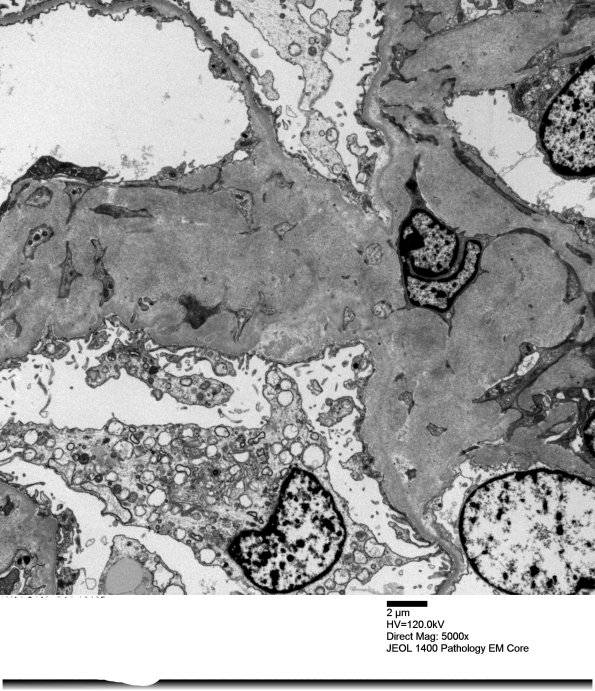

Case 12 History ---- The patient is a 62-year-old man with hypertension and Guillain-Barre syndrome. Operative procedure: Left native kidney biopsy. ---- The glomeruli show marked mesangial expansion and segmentally thickened capillary loops due to the presence of amorphous proteinaceous material that is PAS and silver negative. Focal amorphous proteinaceous material is observed in the arteries. Arteriolar hyalinosis is not seen. A Congo red stain was performed and shows diffuse amyloid deposits within the glomeruli, vessels, and interstitium. ---- 12A1,2 Amyloid deposition in the kidney. At higher magnification the amyloid width is 9-10nm. (electron micrograph)